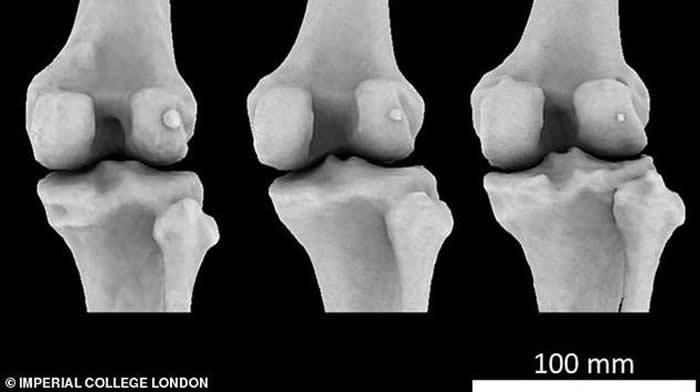

图中显示3个不同膝骨样本存在不同大小的豆骨。科学家发现1918年全球11.2%居民体内存在豆骨,但截至2018年,全球39%居民体内存在豆骨。

英国伦敦帝国理工学院的研究人员回顾了过去150多年进行的2.1万多项科学研究,其中包括研究人员扫描和解剖鉴定发现豆骨的存在。他们从中发现1918年全球11.2%居民体内存在豆骨,但依据发表在《解剖学杂志》的这篇评论报告,截至2018年,全球39%居民体内存在豆骨。

伯托姆博士称,当远古灵长目动物进化成大猿和人类,我们似乎已不再需要豆骨,现在它只会给我们带来麻烦,但有趣的是,近年来人体出现豆骨的概率骤增。这项最新研究发表在《解剖学杂志》上,作者详细研究了25个国家21676个膝盖数据,最早的数据可追溯至1875年。这些膝盖数据来自多种渠道,其中包括:X射线、核磁共振扫描和局部解剖。